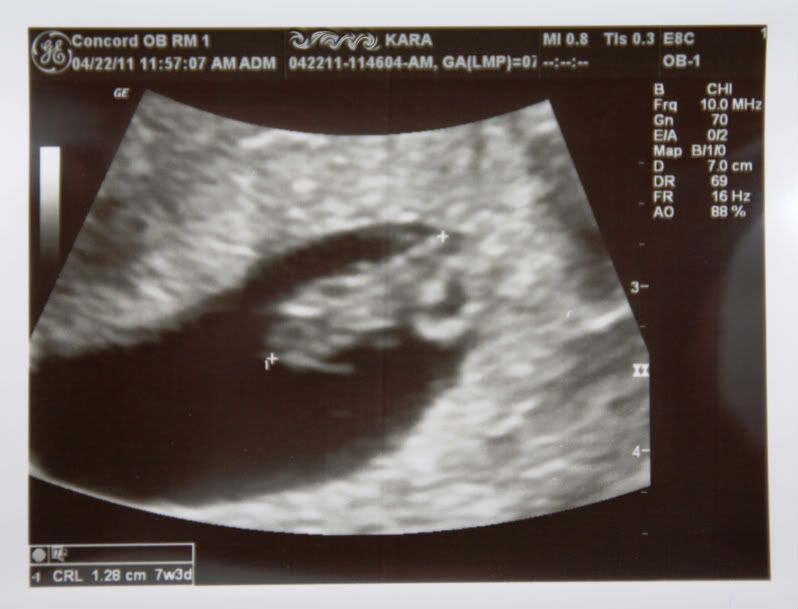

ladies, I want to introduce you to Squishy:

I have been dying to tell you all but I wanted to wait until after my first appt (which was Friday). I will be 8 weeks tomorrow - I'm due December 6!! We are so thrilled and excited for our new family member to be here for Christmas ![]()

We had a dating ultrasound on Friday and everything was perfect - Squishy (a la Finding Nemo) is measuring right on track and we could see the little heart beating (149 bpm). It was amazing.